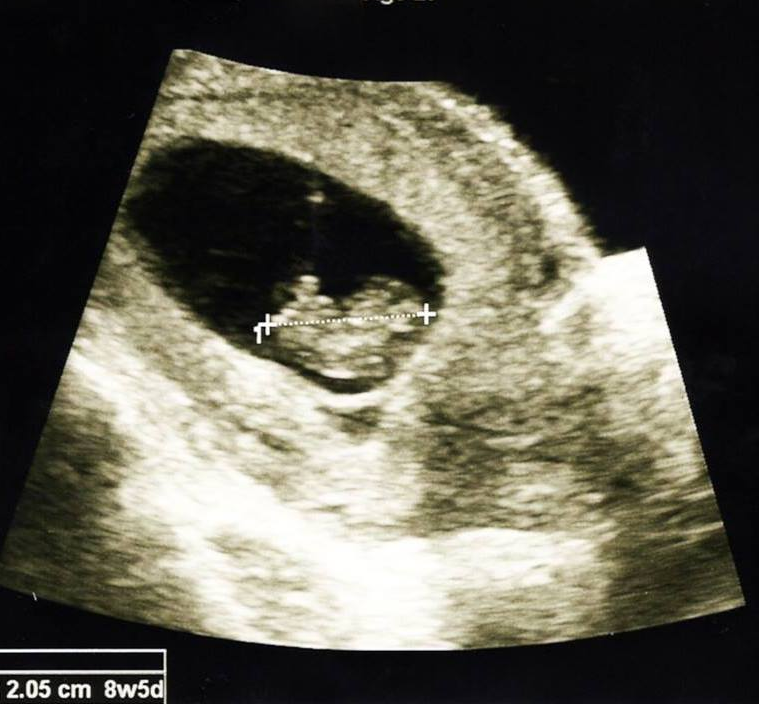

My uterus is nice and roomy, cervix closed, fetal heart rate 172, measured 8w5d, 2.05 cm.  Official due date is May 17, 2015!